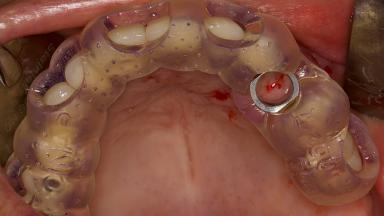

In this short microlearning module on digitally guided sinus floor elevation, we delve into a specialized aspect of the digital workflow for implant-guided surgery, focusing on the use of digital guides in the sinus floor elevation technique.

- explore the intraoperative use of digital guides in SFE